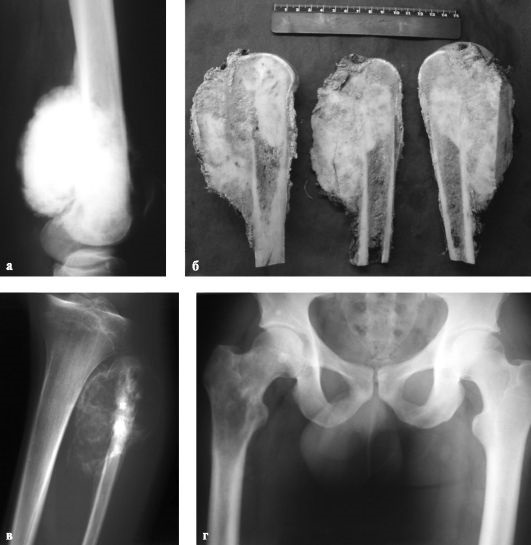

Рентгеновские снимки саркомы плечевого сустава